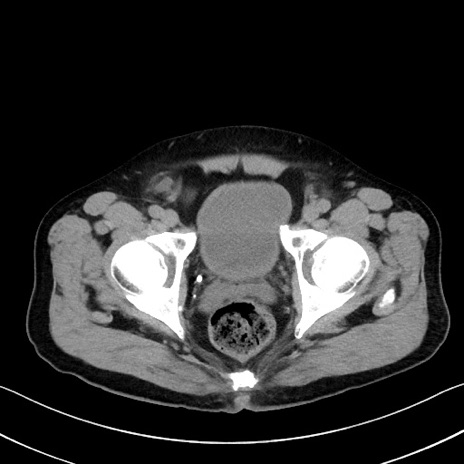

症例35(横断像)

【症例】70歳代 男性

【主訴】腹部膨満、嘔吐

【現病歴】昨日より腹部膨満感出現。本日増悪し、仙痛出現。嘔吐あり、受診。

【既往歴】糖尿病、胆摘後

【身体所見】BP 149/80mmHg、HR 74/min、BT 35.9℃、腹部:膨満、軟、圧痛なし。腸雑音減弱あり。上腹部正中切開瘢痕あり。

【データ】WBC 13500、CRP 1.72